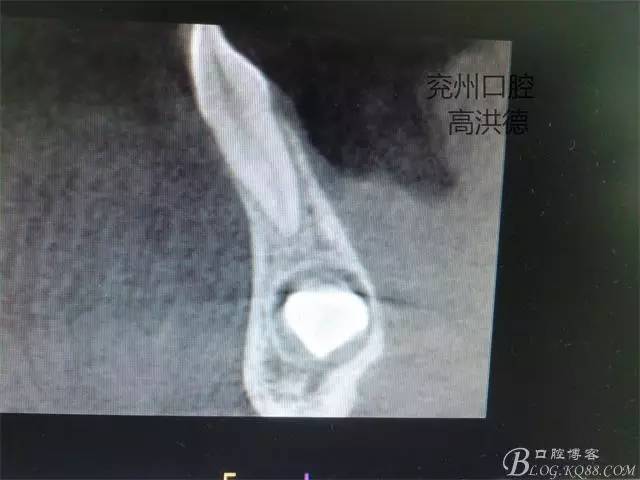

矢狀位